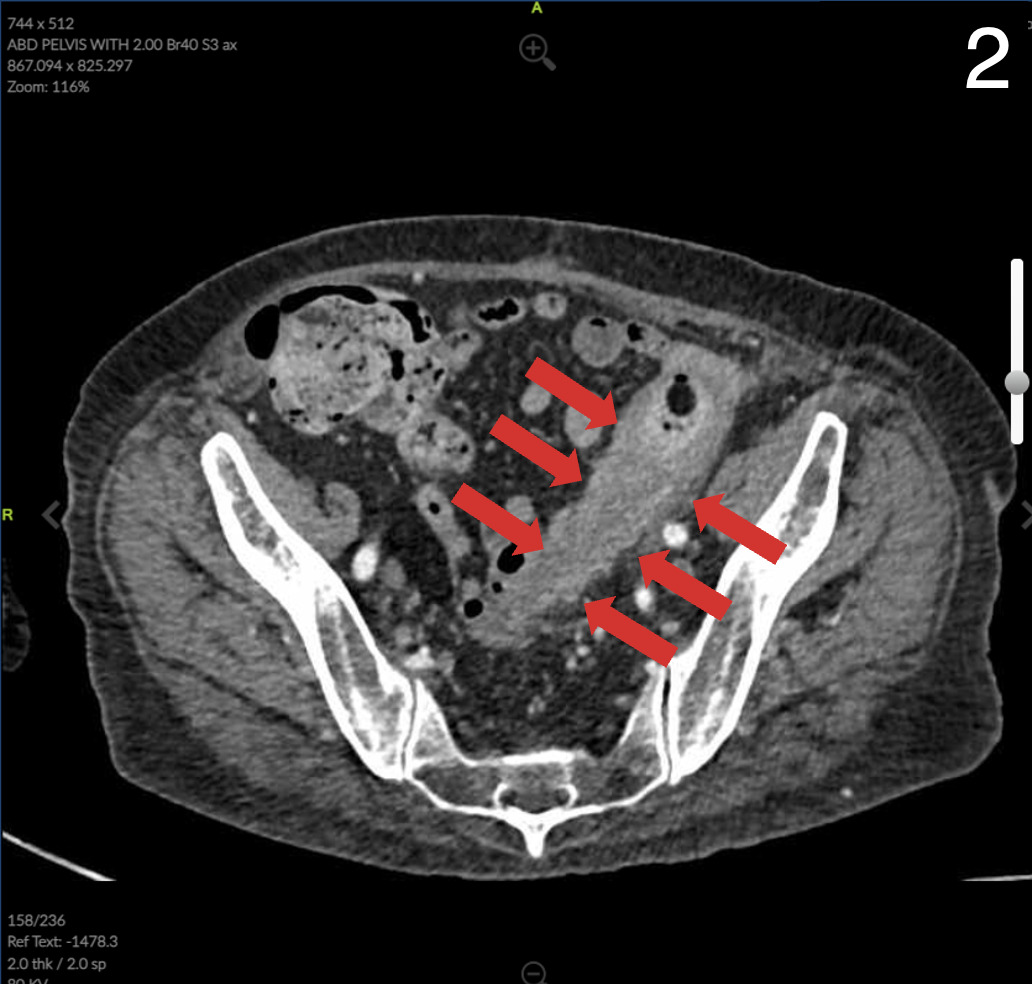

Computed Tomography (CT) of the abdomen and pelvis showed colonic wall thickening particularly in the pelvis close to the vaginal vault. A colonoscopy revealed a severe kink that could not be crossed in the sigmoid colon and extensive diverticular disease.

Pathology of the colonic portion of colovaginal fistula revealed severe acute on chronic diverticulitis with stricture, perforation, and fibrinous serositis with adhesions consistent with clinical history of colovaginal fistula negative for dysplasia or malignancy. The anastomotic donuts were benign and viable colonic mucosa was negative for dysplasia or malignancy. Review of microbiology of the vaginal canal revealed detection of only normal vaginal flora that was negative for G. vaginalis, T. vaginalis, N. gonorrhoeae, C. trachomatis, and C. albincans.